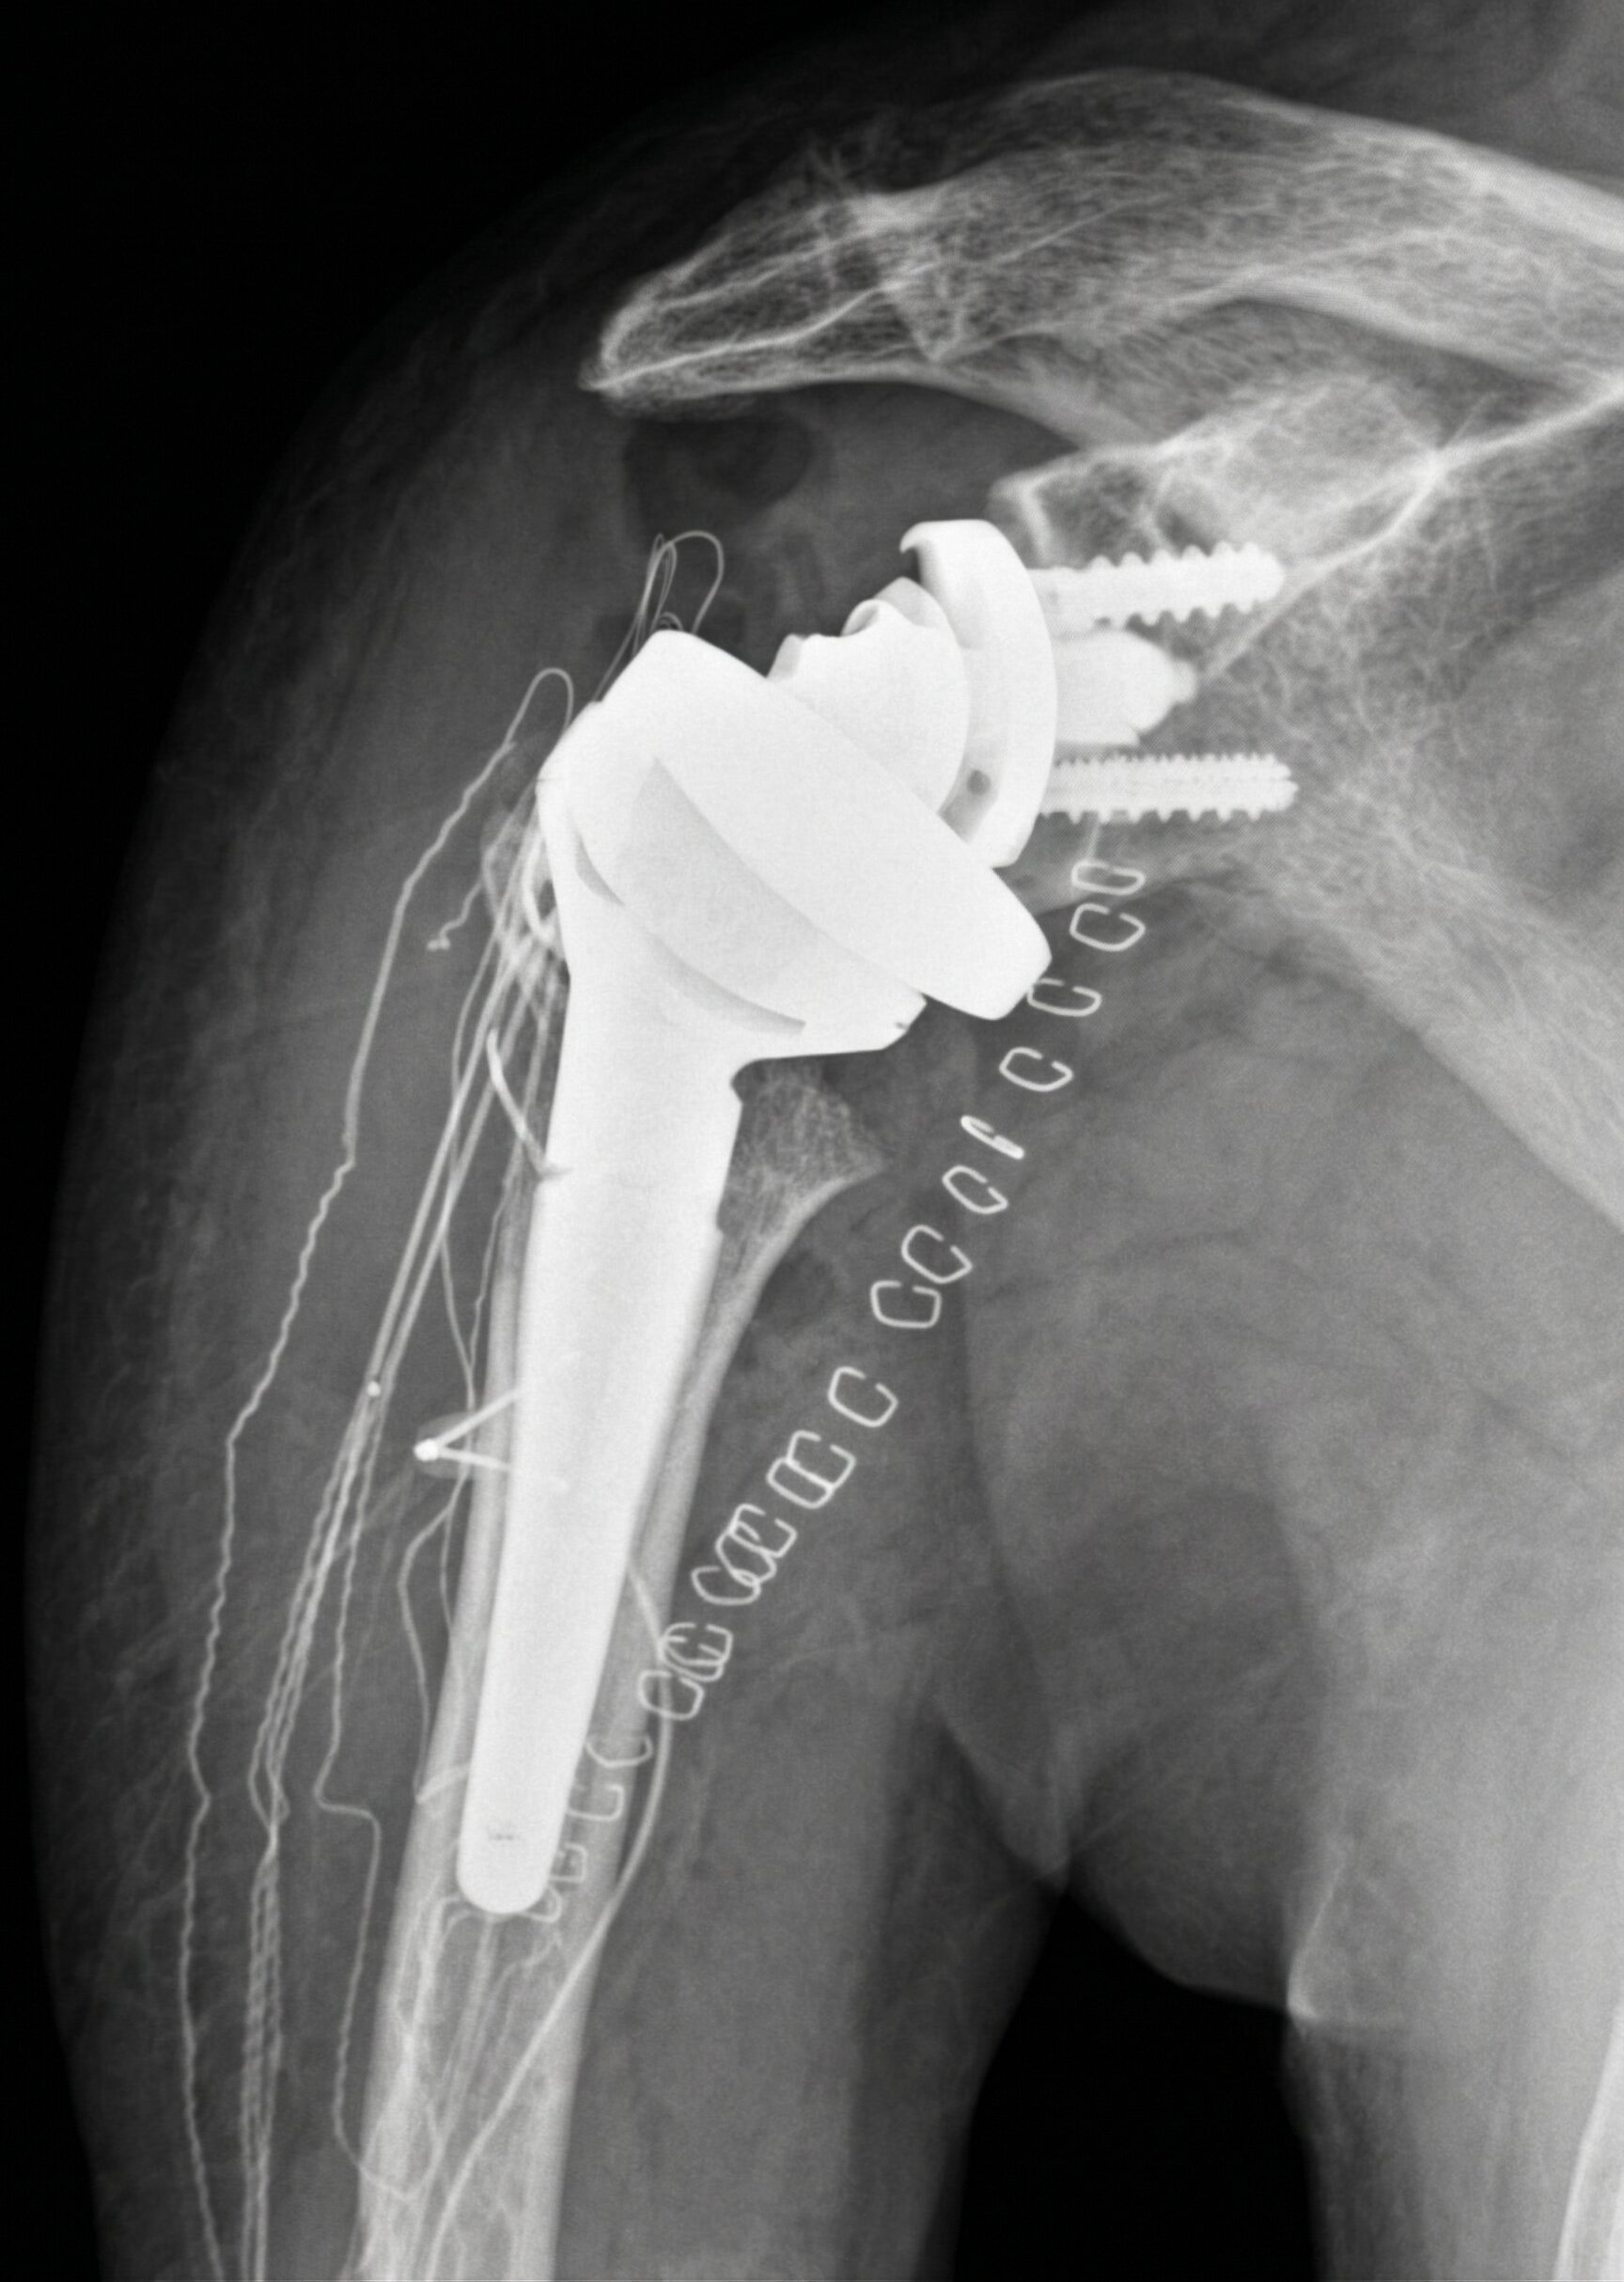

Omartrosi: Protesi di Spalla

È una forma di artrosi della spalla che causa dolore cronico e perdita di movimento, spesso associata a lesioni non riparabili della cuffia dei rotatori.